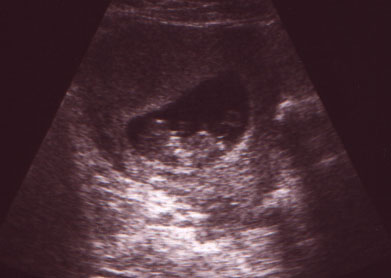

Well, I am pregnant. I've been waiting to post until after I had my u/s to make sure everything was off to a good start. As some of you may know, this is my 5th pregnancy. I've had multiple miscarriages. I'm happy to report we saw a baby this time with a beating heart. We got to see the baby bounce and move around. It's been so long since we've had good news, that now we have to let it sink in a bit, that this may result in a baby! (It sounds silly, I know.)I'm due Dec. 10th, although the u/s said sooner.:)

baby

awww...congratulations. The baby is beautiful!!